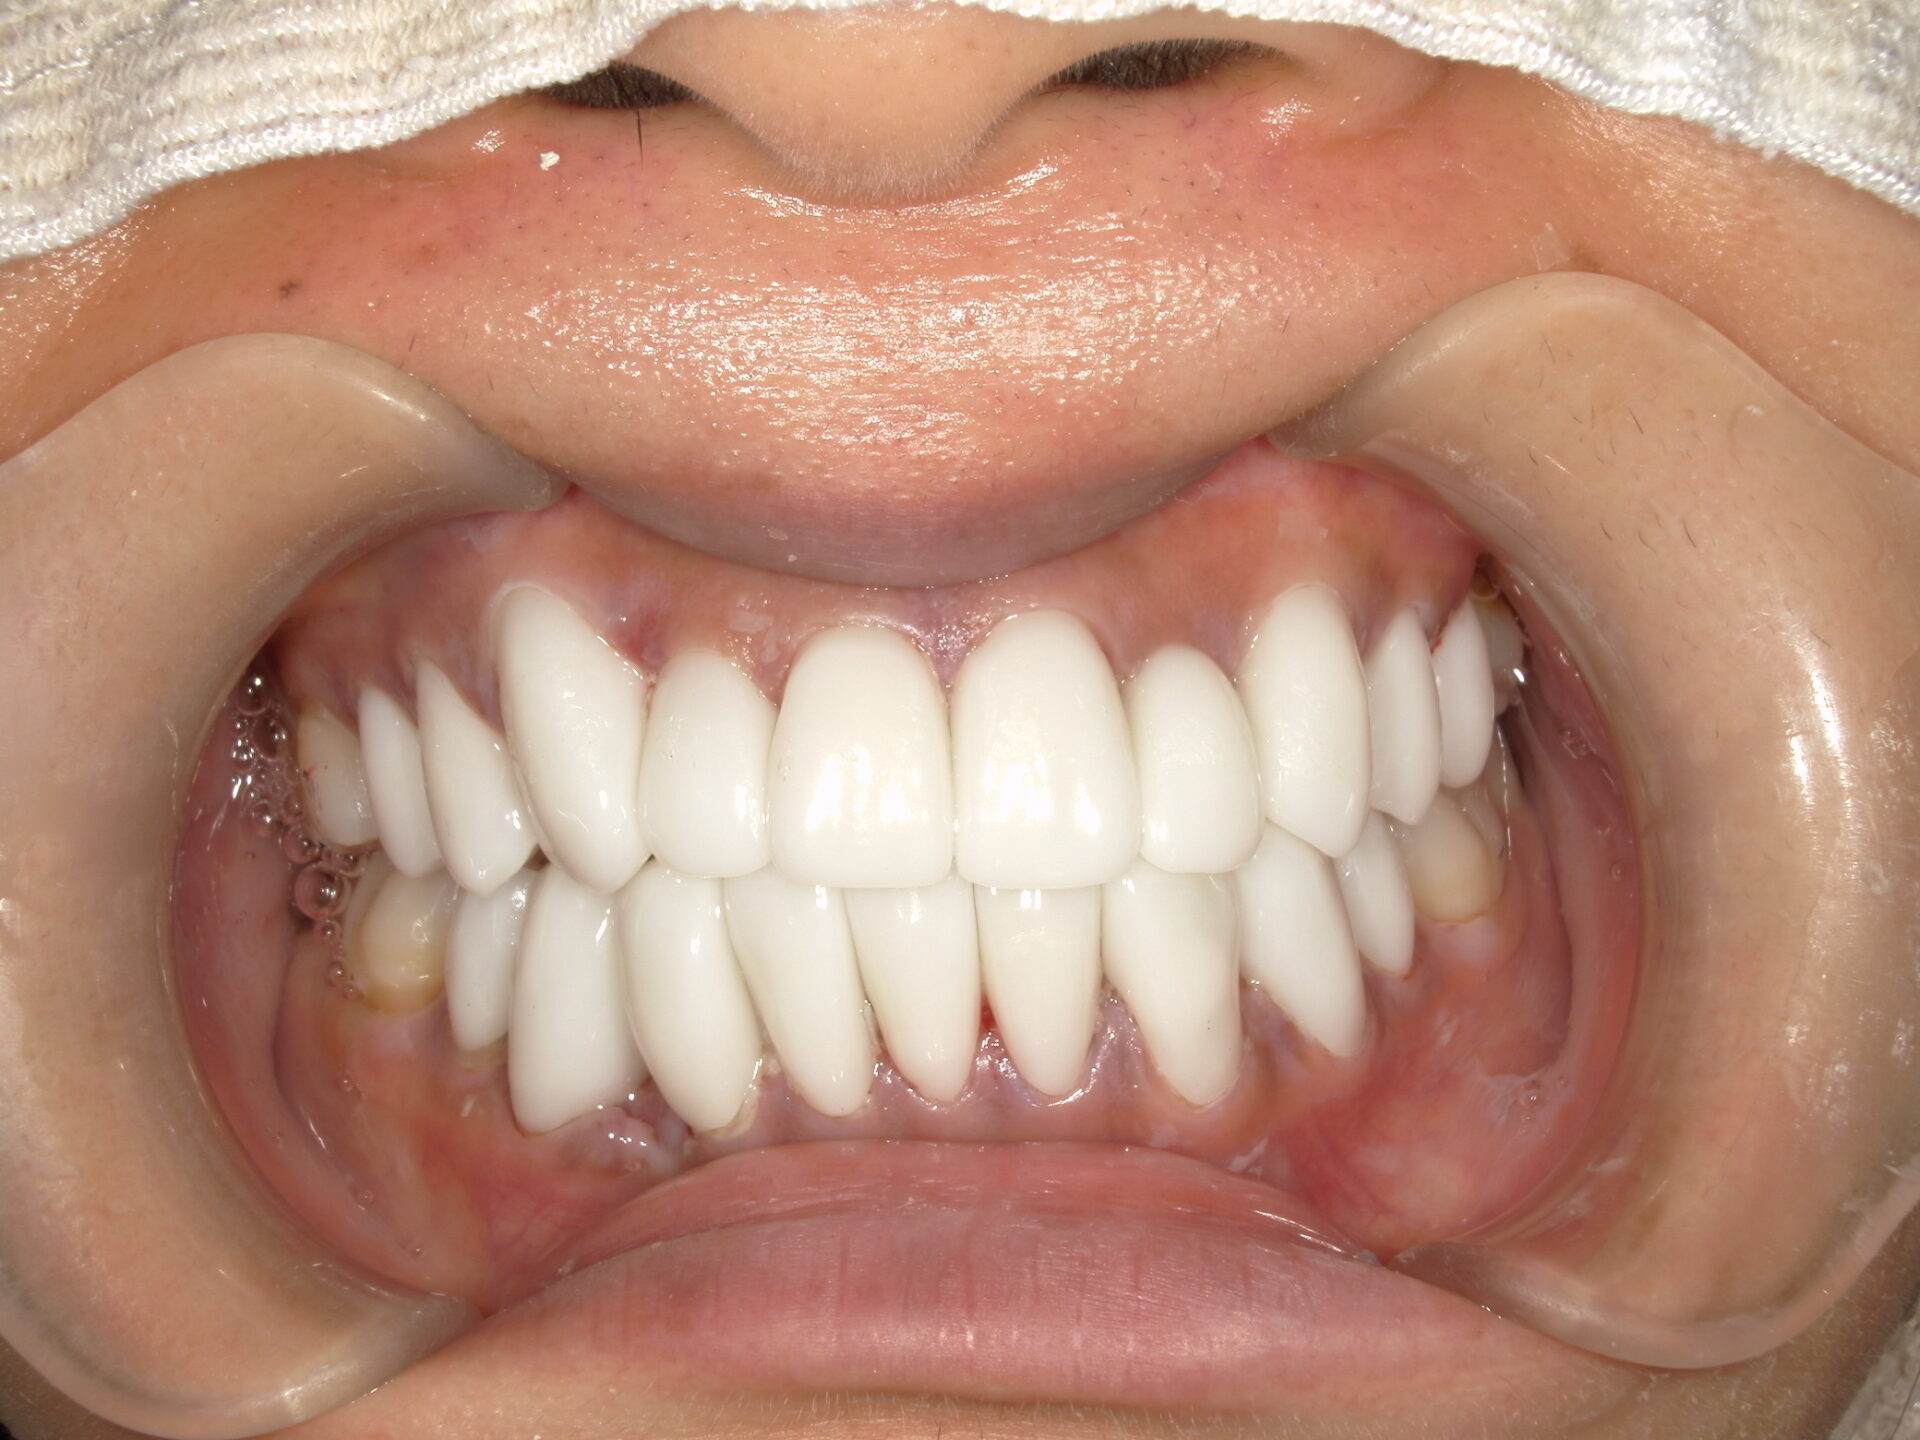

before

after

患者さんの年齢 60代 男性 症状 白い歯を入れて噛めるようにしてほしい 治療内容 インプラント治療(オールオン4) 費用 費用900万(税抜) 治療期間・回数 治療期間2年・通院回数12回 メリット なんでも噛める 見た目が綺麗になった デメリット・リスク 骨造成などで費用が増える場合がある - インプラント治療